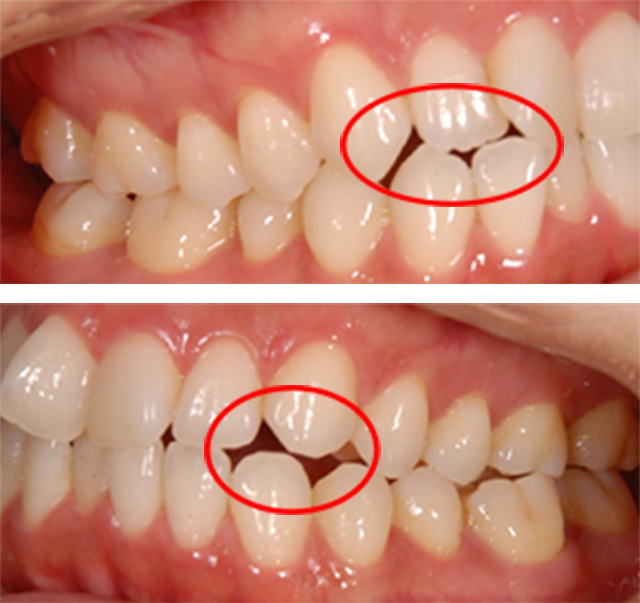

| 治療回数 | 36回 |

|---|---|

| 年齢・性別 | 30代 女性 |

| 治療期間 | 1年10ヶ月 |

| 治療費用 | 990,000円(税込) |

| 調整費 | 6,600円×来院毎(税込) ※2年目から |